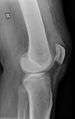

| An x-ray demonstrating quadriceps tendon rupture. Note the abnormal angle of the patella and soft-tissue swelling marked by the arrow. | |

A quadriceps tendon rupture is a tear of the tendon of the major leg extensor (rectus femoris), usually close to its insertion at the superior pole of the patella.